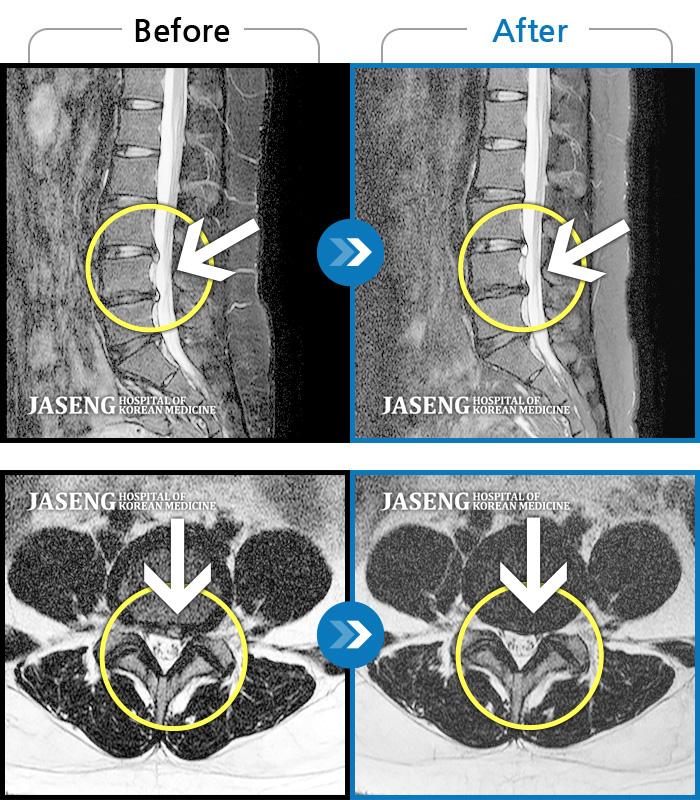

허리디스크

인천 · 강아현 원장

좌측 허리 통증 및 골반 통증이 심하여 걷는 것도 힘든 상태로 내원하셨습니다.

촬영시기

2024.05.08 ~ 2025.11.12

2025.11.14

조회수 128